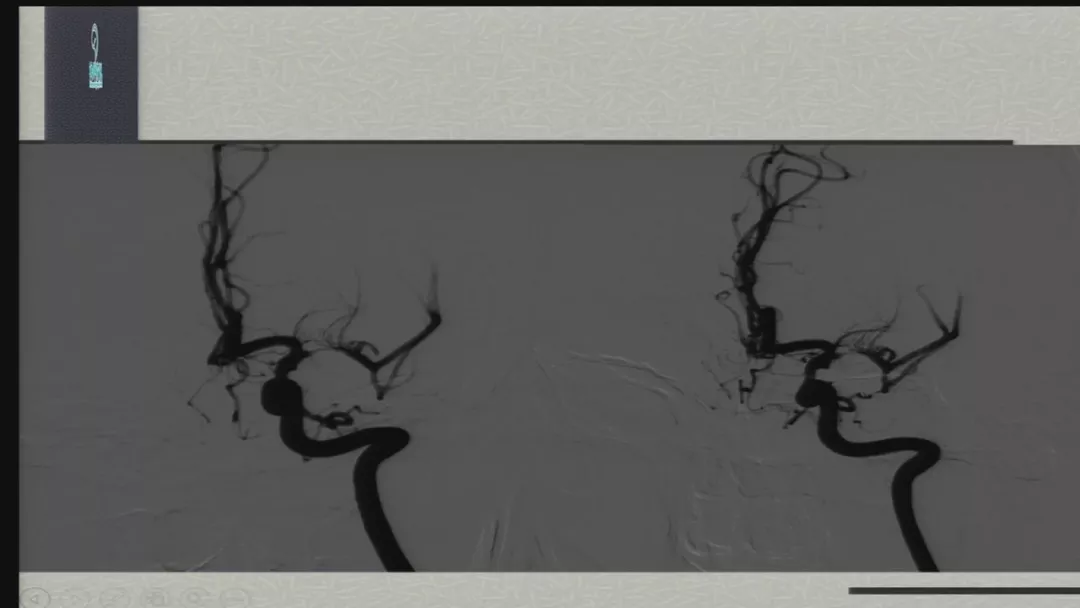

徐浩文:Neuroform EZ在ICAS治疗中的应用丨第七届全国介入医学工程大会精彩回顾

今天为大家分享的是由郑大一附院徐浩文教授在第七届全国介入医学工程大会上带来的“Neuroform EZ在ICAD治疗中的应用”精彩讲课视频和PPT,欢迎观看!(内容未经讲者审核,不当之处请与我们联系)